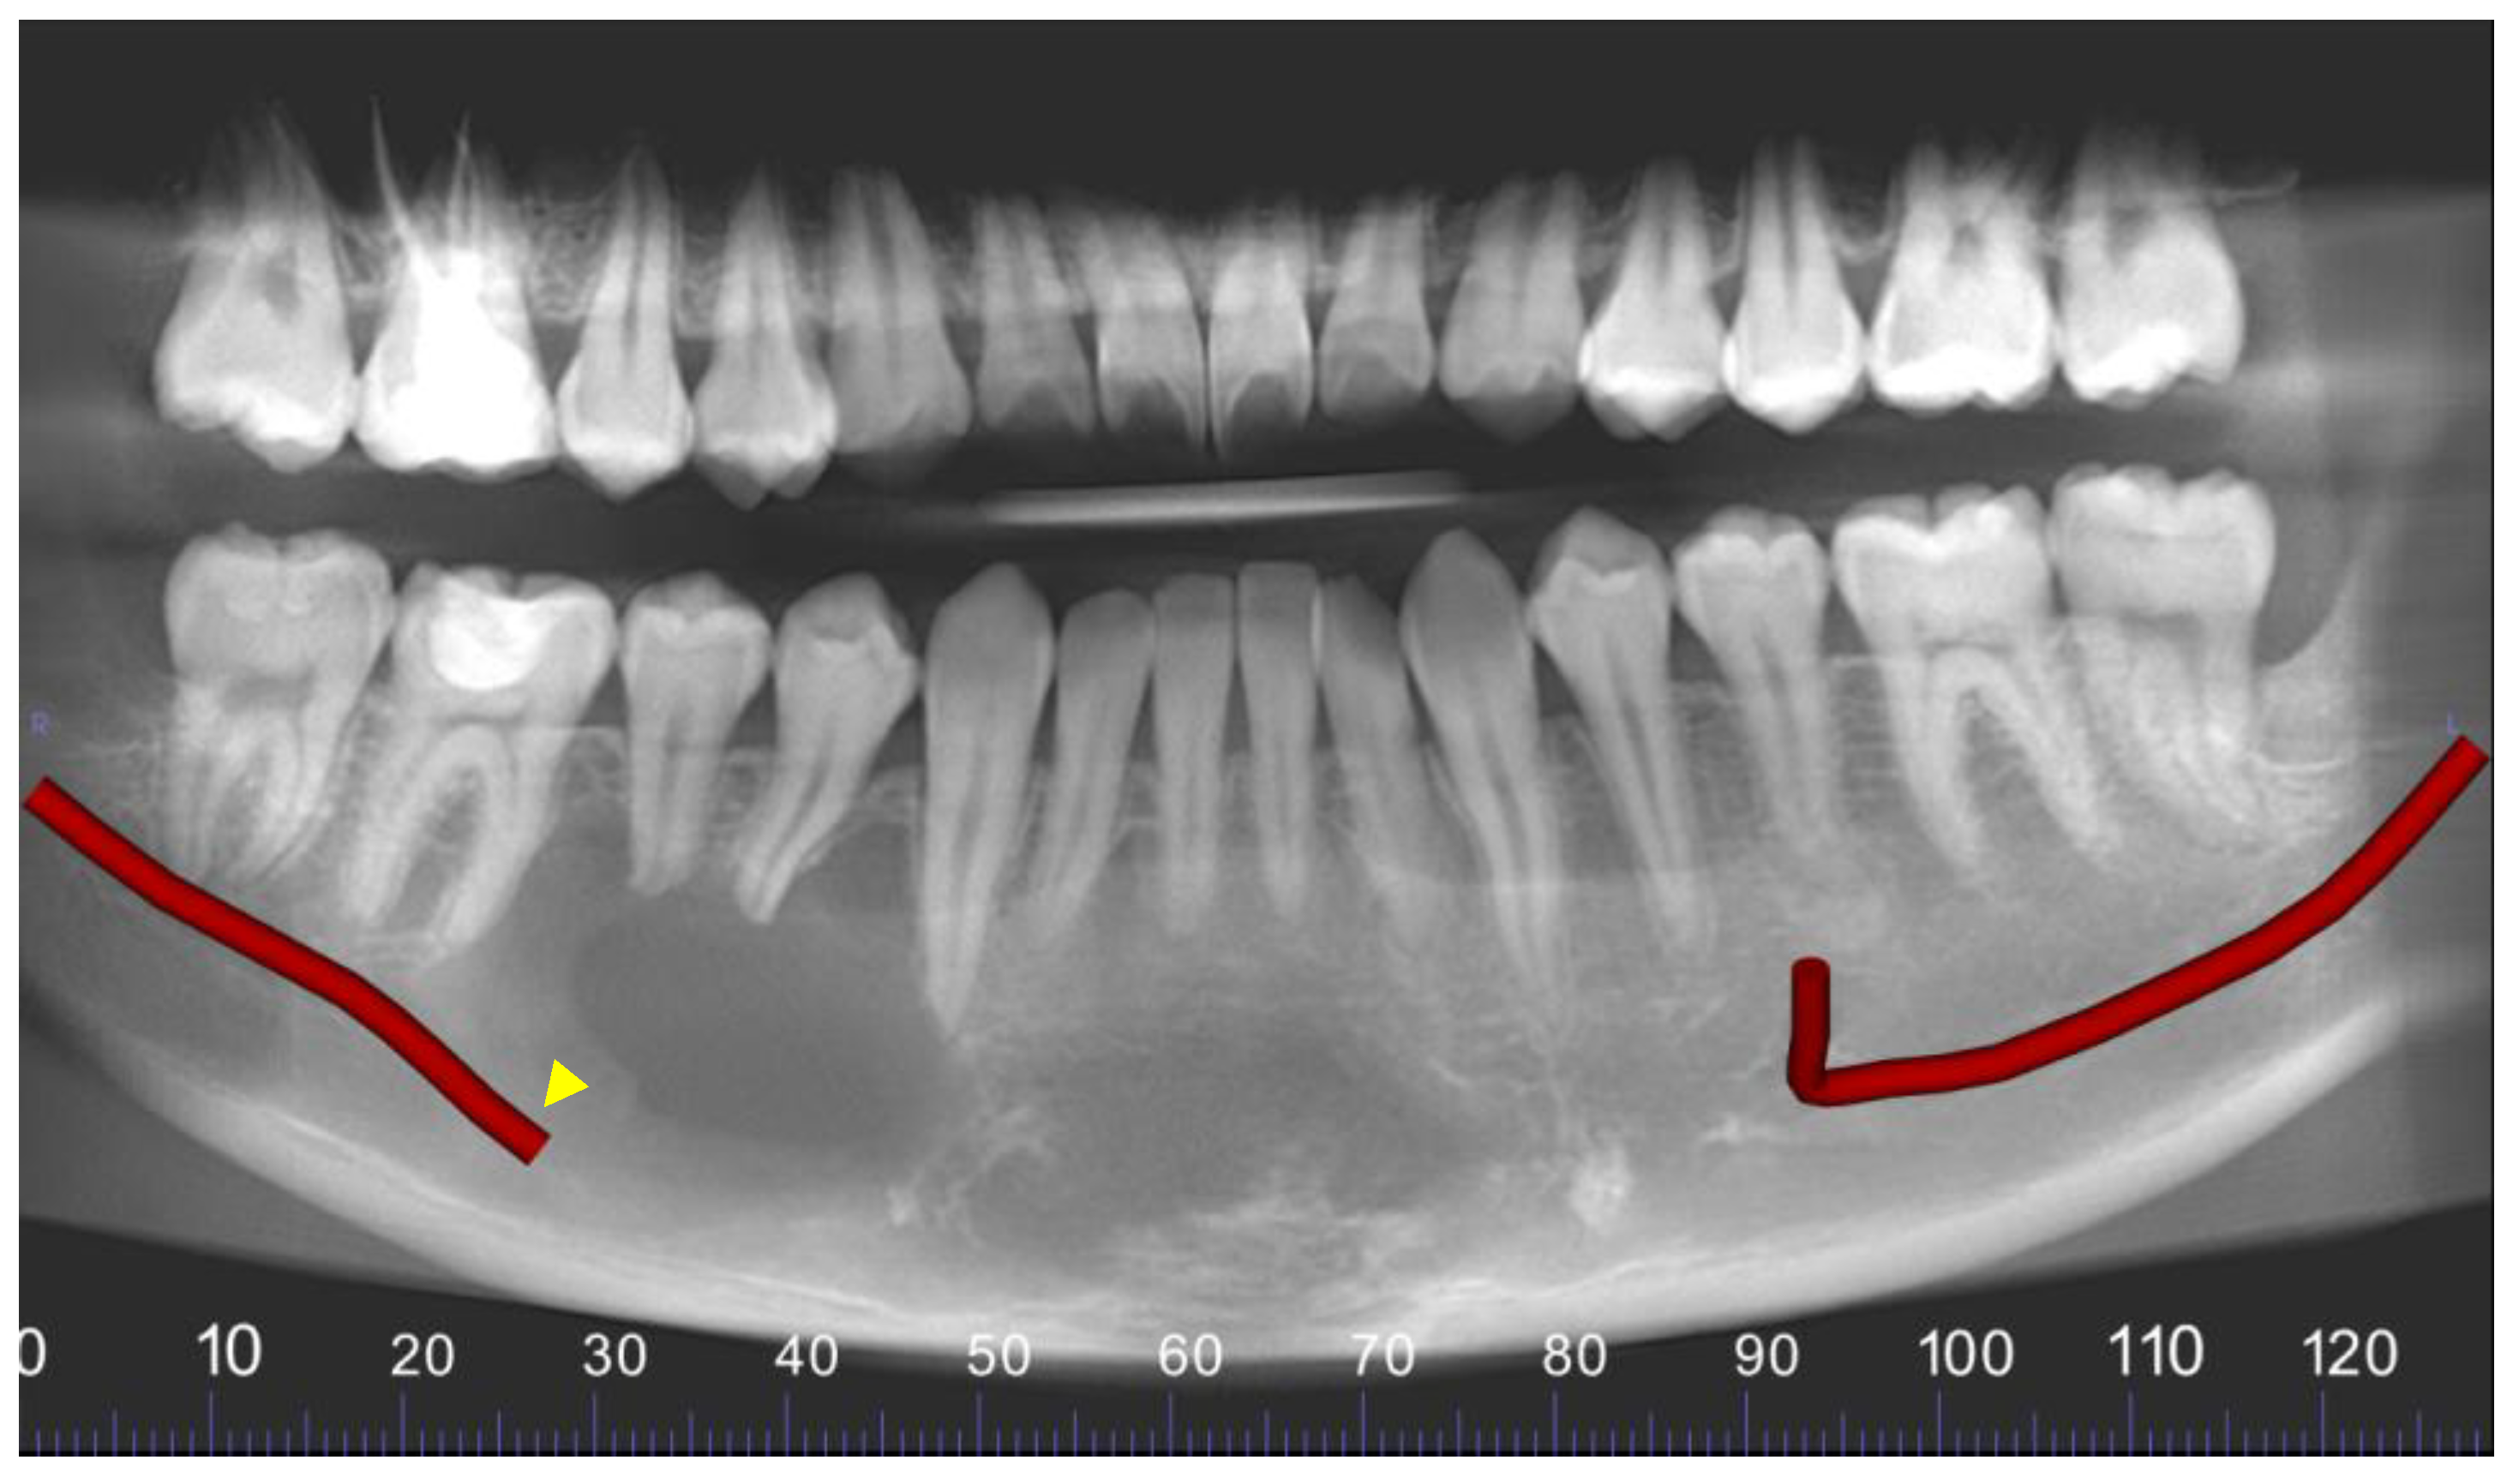

Figure 5. Panoramic reconstruction of the volume. The right inferior alveolar canal is interrupted and displaced inferiorly (yellow arrowhead).